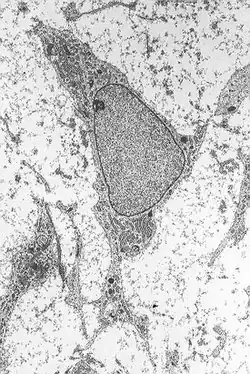

Mezenchymální kmenová buňka

Mezenchymální kmenová buňka (MSC) je multipotentní buňka schopná obnovovat poškozené mezenchymální a krvetvorné tkáně. Je schopná se měnit (diferencovat) na široké spektrum buněčných typů, jako je chondrocyt, adipocyt, osteocyt, osteoblast, myocyt, kardiomyocyt, neuron či inzulin produkující buňka.[1] Mezenchymální buňky jsou proto vhodnými kandidáty pro použití v regenerativní medicíně a buněčné terapii.[1]